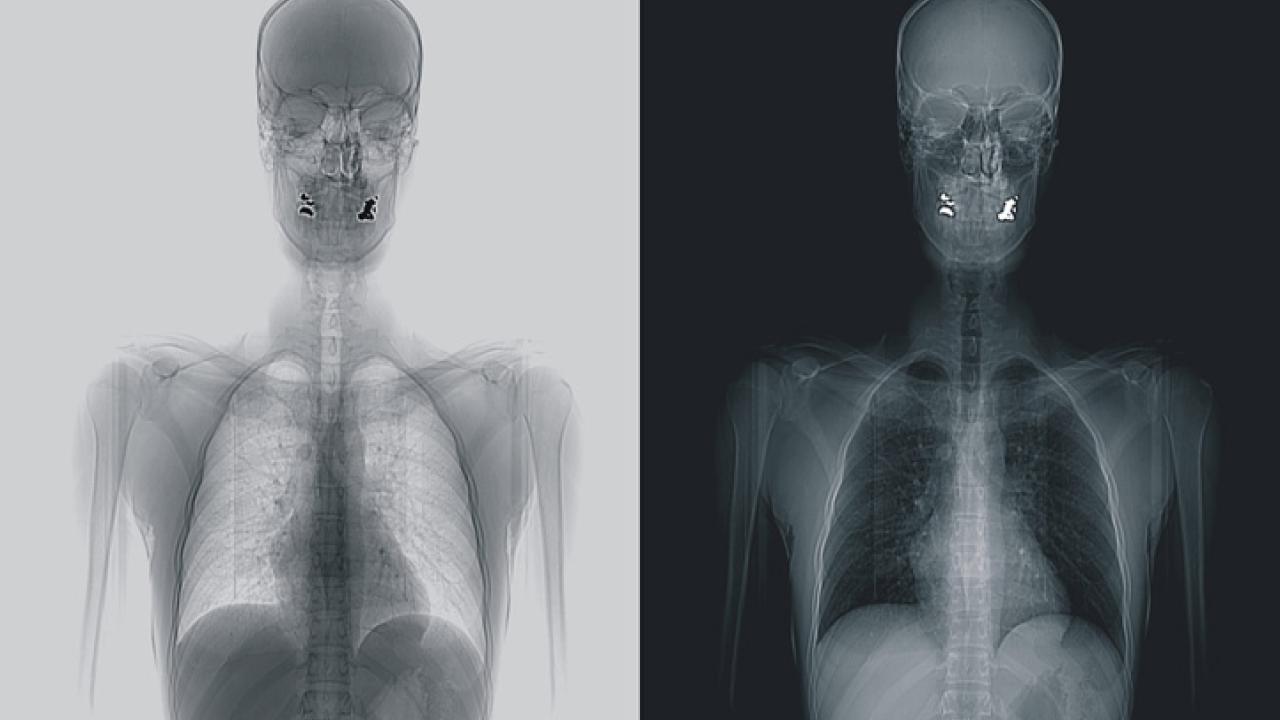

På bilden går det utmärkt att utläsa kroppens former, om än inte ner till minsta detalj. För att komma runt det integritets-kränkande problemet menar tillverkarna att kontrollanterna som undersöker bilderna kan sitta i ett annat rum än resenärerna som skannas. Ett argument som kritikerna anser vara för svagt. Risken för att bilderna sprids på annat sätt, genom internet till exempel, bedöms också vara för stor.